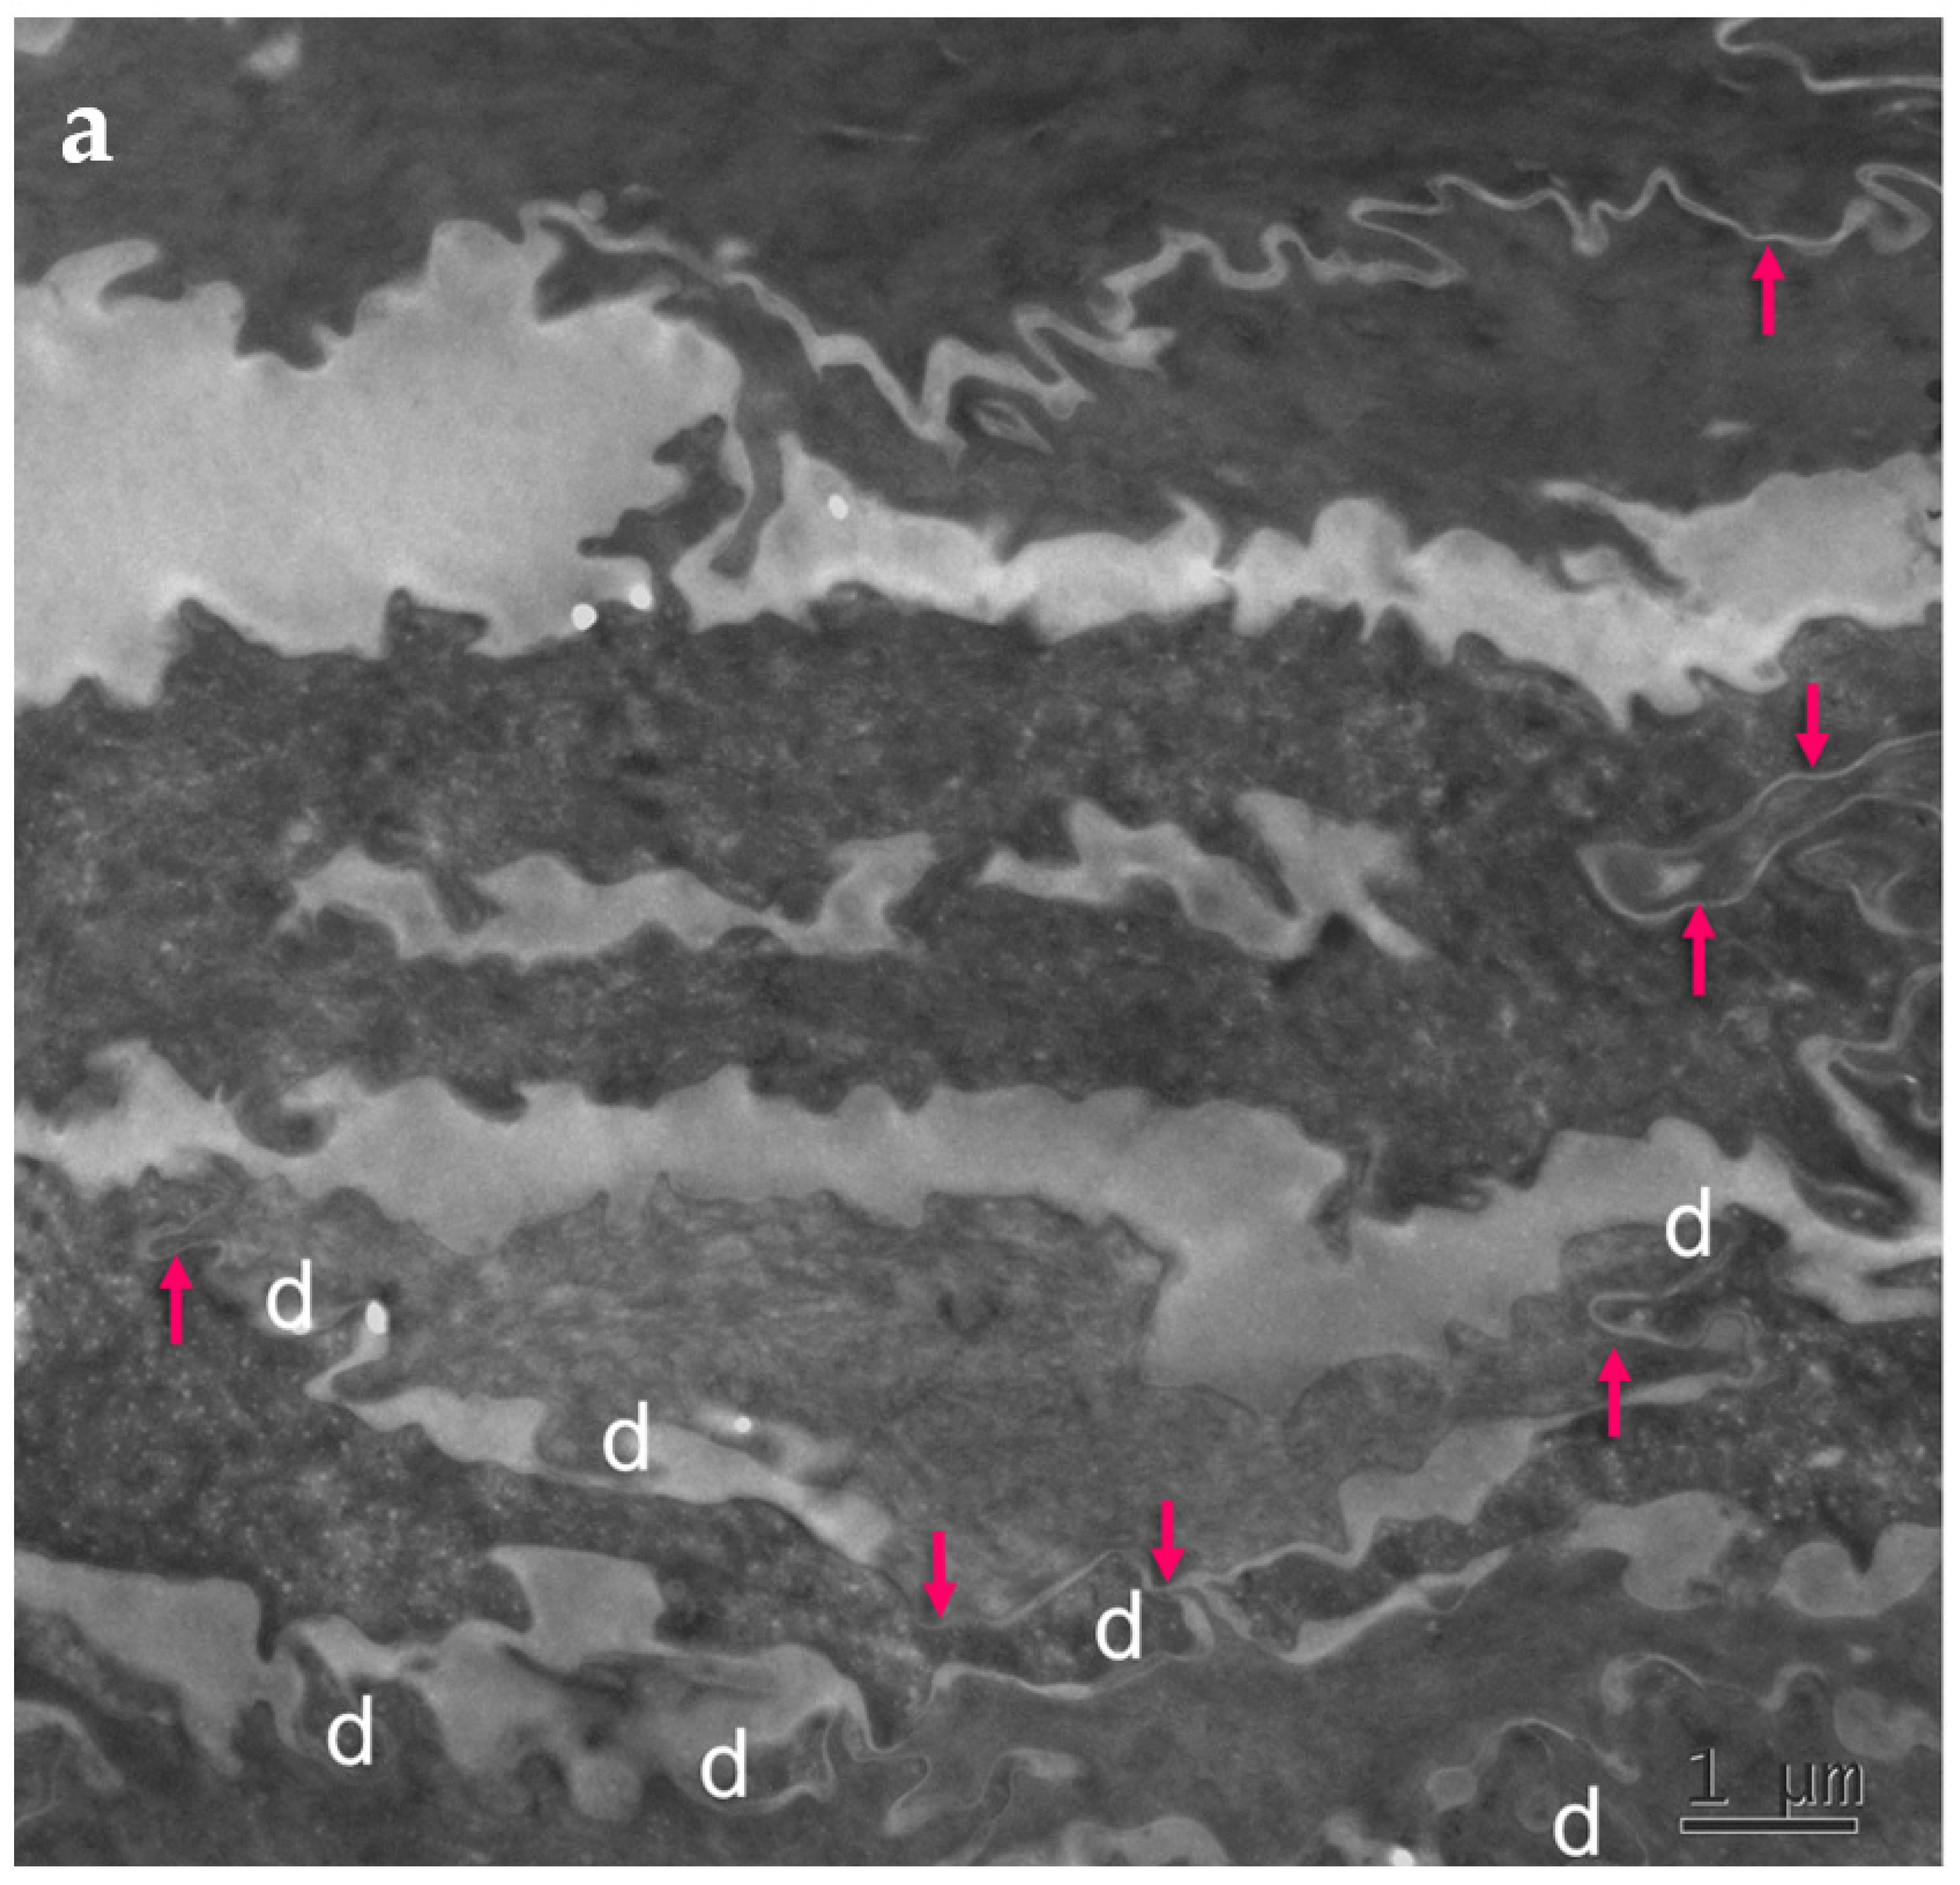

Figure 4.

Ultrastructural features observed in the SC of PSD include paucity of corneodesmosomes (d) that rapidly disappear from the lower parts of the horny layer, as seen in (a), and upregulation of expression of TJ-derived intercorneocyte “fusions” (arrows). (b) In the upper SC, the remaining corneodesmosomes (d) are often found in the proximity of the TJ-derived riveting structures (arrows). Bars = 1 µm in (a); 0.5 µm in (b).

The cell–cell fusions of lipid envelopes in the upper part of the lateral intercorneocyte contacts, which have been shown to result from the persistence of TJ structures, were quantified and the results compared with the situation in 35 normal controls (Table 4).

Fraction of the apical-lateral contacts between corneocytes showing “fused” morphology in the SC of PSD. NHS = normal human skin.

Upregulation of the TJ-derived corneocyte envelope fusions in PSD may represent a compensatory phenomenon in face of corneodesmosome fragility. It may contribute to cohesion in the upper SC directly, through enhanced cell–cell adhesion, and indirectly, by hindering access of extracellular hydrolytic enzymes to corneodesmosomes.

Mature upper SC is more rigid than living epidermis and lower, freshly cornified keratinocytes [40]. In this situation, minor mechanical insults to tissue lacking reinforced corneodesmosomes may provoke a preferential split at the interface between the two parts. The upper part of the horny layer of PSD appears to be reinforced by the increased presence of cross-linked TJ remnants.